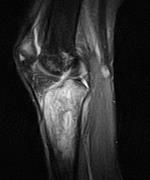

4.jpg

矢状位片

T1加权像

股骨外侧髁前外侧面、胫骨近端及髌骨上极可见异常信号(T1加权像低信号,T2/PD脂肪抑制序列呈不均匀高信号)浸润性病变,伴有边界不清的过渡带。可见少量骨外成分。